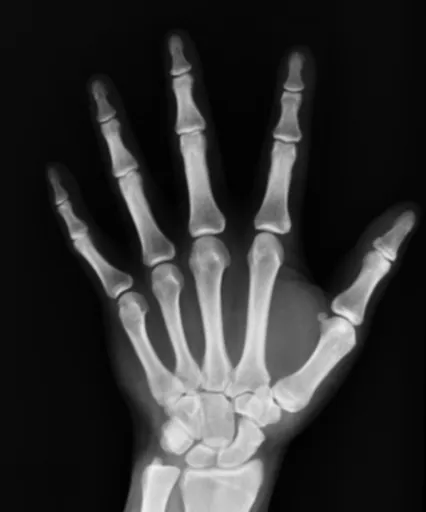

원발성 다한증은 특별한 원인 없이 발생하는 다한증입니다. 주로 손, 발, 겨드랑이, 얼굴 등 특정 부위에서 땀이 많이 나는 것이 특징입니다. 신경계의 과민 반응이 원인으로 추정되지만, 정확한 원인은 아직 밝혀지지 않았습니다. 젊은 연령층에서 많이 나타나며, 가족력이 있는 경우 발생 확률이 높아지는 경향이 있습니다. 원발성 다한증은 일상생활에 불편함을 초래할 수 있지만, 건강에 직접적인 위협을 가하지는 않습니다.